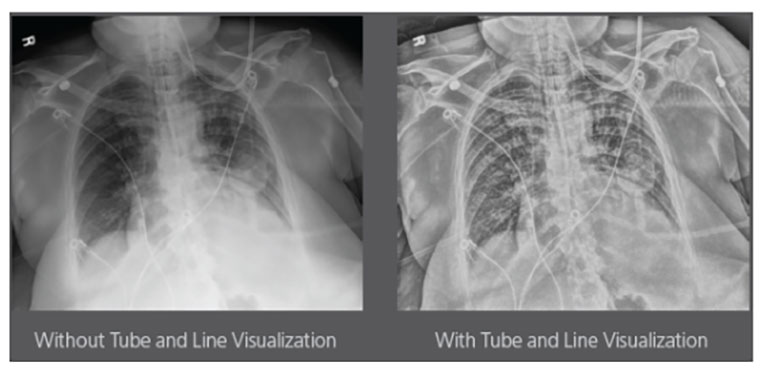

CARESTREAM Image Suite V4 MR11 has set a new standard for workflow efficiency, offering a robust set of features and functionalities to enhance clinical confidence in healthcare professionals. Using an auto-generated companion image from a single exposure, leverage a range of image processing options to increase diagnostic accuracy and enhance patient care.

Carestream Introduces New Software Update to Boost Diagnostic Accuracy

Carestream today announced the latest update to its Image Suite V4 Software, MR 11: a series of enhancements to help improve customer confidence and increase diagnostic accuracy [...]